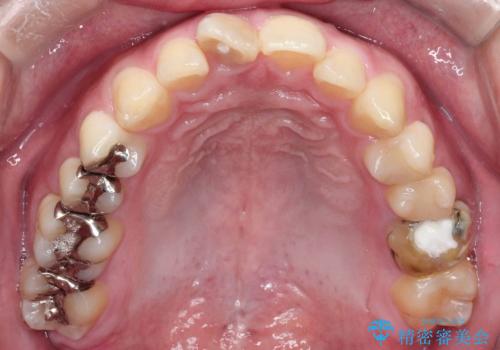

- 「上の前歯の捻じれと下の前歯のでこぼこを治したい」を主訴に来院された患者様です。

矯正検査の結果、非抜歯で矯正可能だったためインビザラインで治療を行いました。

アーチの拡大とIPRで叢生を改善いました。

11ヵ月で矯正を終える事ができ患者様も大変ご満足されていました。